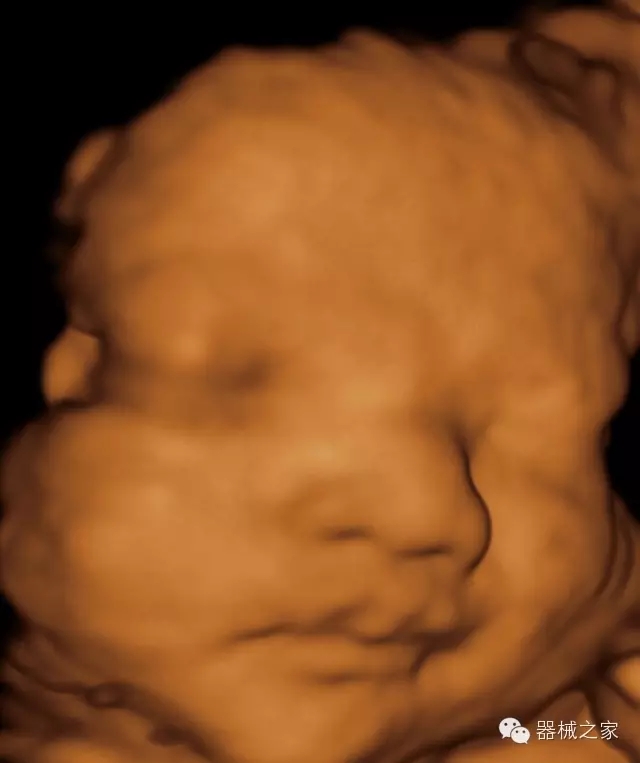

臨床圖片賞析

·完整的3D/4D臨床應(yīng)用,STIC, MCUT 和Auto NT等滿足產(chǎn)科所有應(yīng)用;

·更高的HQ羊膜腔鏡成像技術(shù)精細(xì)觀察每一個暗區(qū)細(xì)節(jié);